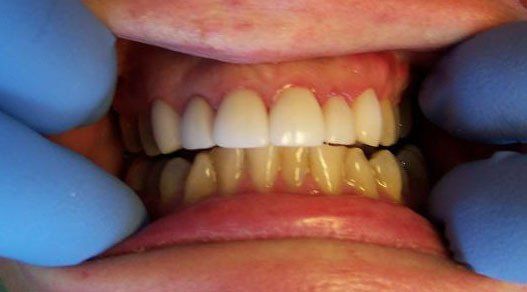

Johnson Before

Button

Johnson After